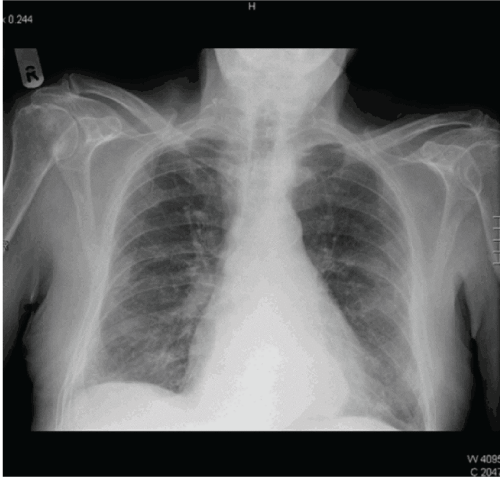

showing

Figure 1: CXR showing right sided pleural thickening.